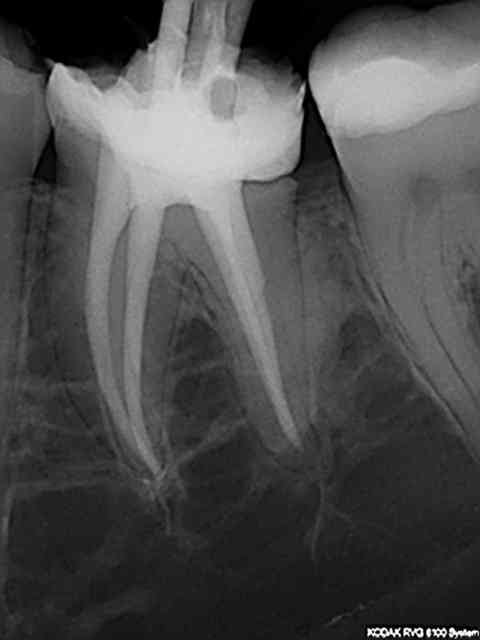

Hier un patient original : quelques onlays ceram en bouche.

Pan lingual fracturé sur 36 (l'onlay est resté en place) et vu qu'on est en france c'est ........ pulpec, puis ic et couronne métal (accroches toi pour lui fourguer un onlay non remboursé). La 16 c'est un autre patient , j'arrive pas à la virer. Elles sont traitées en finition au r40 pas forcément mieux que le r25 mais au moins l'aiguille de la seringue d'irrigation va à l'apex !)

J'ai fais un cas, molaire, ça va bien.

C'est pas une pulpec, c'est une endo, une bio vous dites ?

Dent partiellement nécrosée, carie pulpaire au distal.